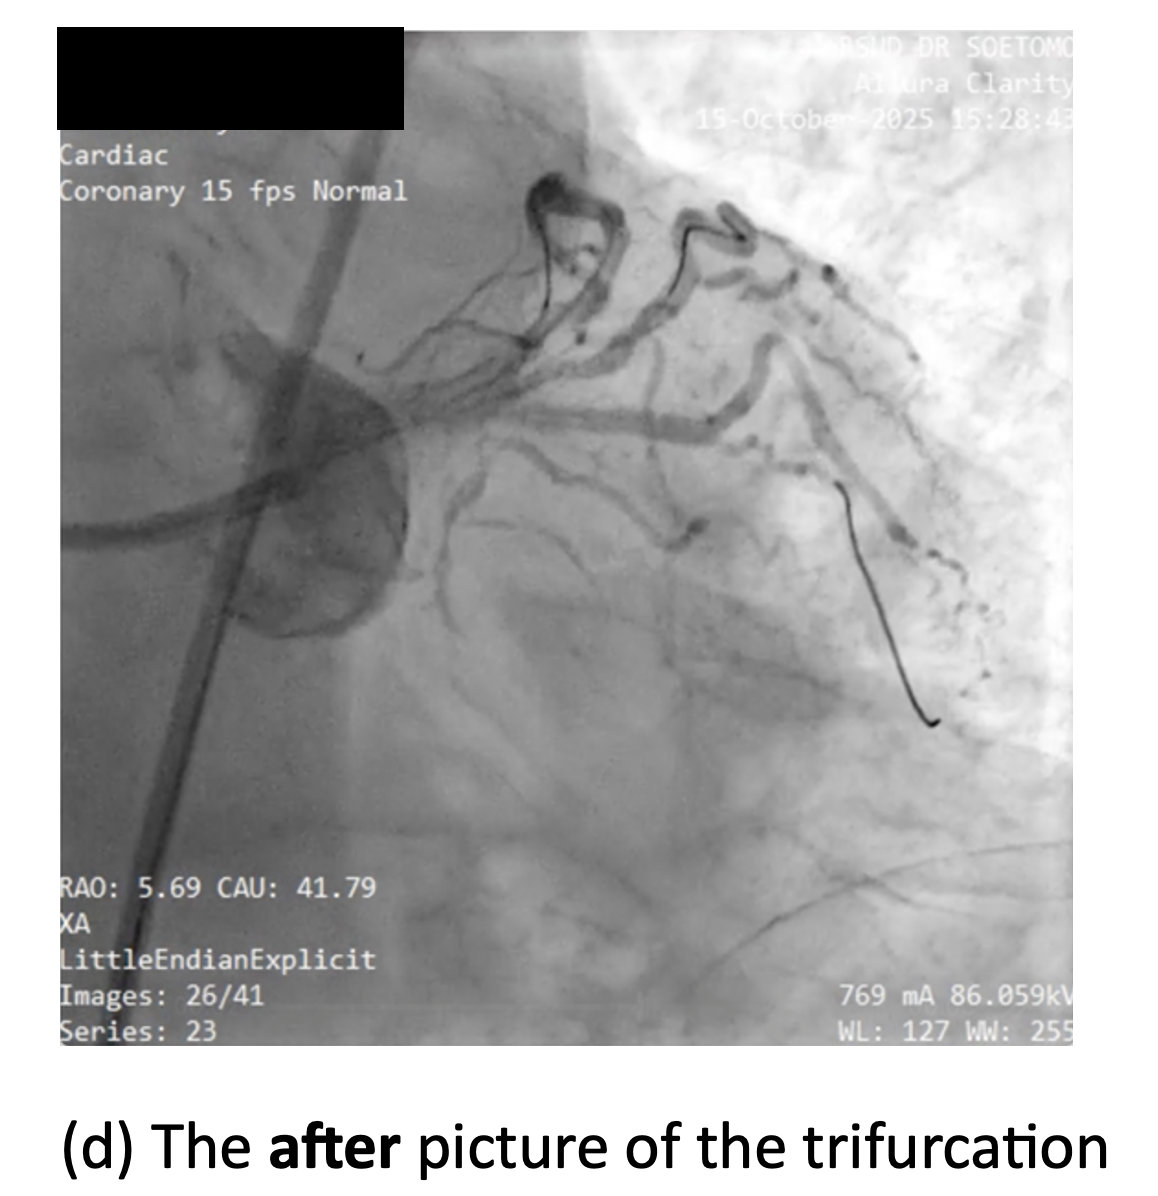

Using right femoral access with 7F long sheath, elective PCI was performed employing a Triple-kissing-balloon (Trissing) technique used for trifurcation lesions. The technique consisted of: (1) Engaging left main with BL 3.0 7F guiding catheter (GC) and guiding wire (GW) to three branches (GW BMW guidewire to LAD, GW Runthrough Hypercoat NS to LCx, and GW Whisper to Ramus Intermedius); (2) Stenting the main vessel with DES Xience Xpedition everolimus-eluting stents (Abbott Vascular, USA) 3.5 ¡¿ 23 mm to distal LM - proximal LAD; (3) Proximal optimization technique (POT) for MB stent; (4) Rewiring and assessment of side branches, followed by T-stenting and small protrusion (TAP) technique at the first side branch with DES Xience Xpedition everolimus-eluting stent 3.0 ¡¿ 18 mm to osteal-proximal LCx; (5) Evaluation of the second side branch, Ramus Intermedius, and followed by second TAP using DES Xience Xpedition everolimus-eluting stent 2.5 ¡¿ 15 mm at ostial-proximal of Ramus Intermedius; complemented by kissing balloon inflation (KBI); (6) Final POT; (7) Third trissing balloon inflation across all three branches to optimize stent apposition. Total heparin administered was 8500 units. Final angiography demonstrated TIMI 3 flow in all vessels with complete revascularization. Total contrast volume 210 mL using Iohexol, with total fluoroscopy time is 45.6 minutes, dose-area product 114 Gy¡¤cm©÷. No periprocedural complications occurred.

Case Summary